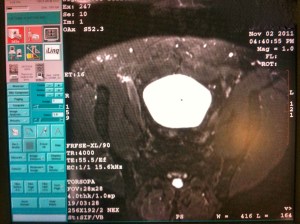

My experience began with the nurse instructing me to undress from the waist down and to lay on my side covering myself with a sheet made from paper. This picked up my spirits a bit as, on some metaphorical level, I found this preferable to having to bend over. If you’re concerned you might get an erection, trust me – you won’t. The experience is overwhelmingly emasculating. I was like a dog with its tail between its legs. She registered my heart rate at 56bpm so I was managing the anxiety fairly well. She then asked for my permission to allow a 3rd party into the room, a woman technician, to train the urologist on their brand new prostate biopsy ultrasound machine and monitor the imaging. Like I was going to say no to that. “No, let the doctor learn as he goes. We’ll learn how to operate this thing together.” While I don’t think of myself as an exhibitionist, I was actually fine with it. The more the merrier.

Dr. Webster was quite good at setting my expectations. The procedure took maybe 20 minutes. While extremely uncomfortable, it didn’t really hurt. The most painful aspect was two needle injections of something to numb my prostate. This hurt on the level of any flu shot to the arm, only it wasn’t to the arm. My online research led me to expect the biopsy pinpricks to feel similar to bee stings. Had the doctor told me this I was prepared to reply, “American bees or African bees?” I’m still a little disappointed I couldn’t reference that Monty Python skit. Reminds me though, I need to erase my search history.

I received 12 biopsies and only two of them hurt a little, but less so than the initial shots. After the fourth biopsy, my penis began to burn – acute dysuria. The sensation was fairly strong actually and maybe hurt more than those two initial shots. Apparently, this is normal, I’m guessing from a dramatic change in the pH balance suddenly streaming through my urethra. In other words – bleeding. I should have asked what causes it because I’m just guessing. Feels better this morning. Dr. Webster told me I would jump at the first biopsy – which I did – but I didn’t overreact to any of the subsequent biopsies. Each biopsy made a clicking noise like a cap gun being fired, or a mousetrap being sprung. It’ll spook you the first time.